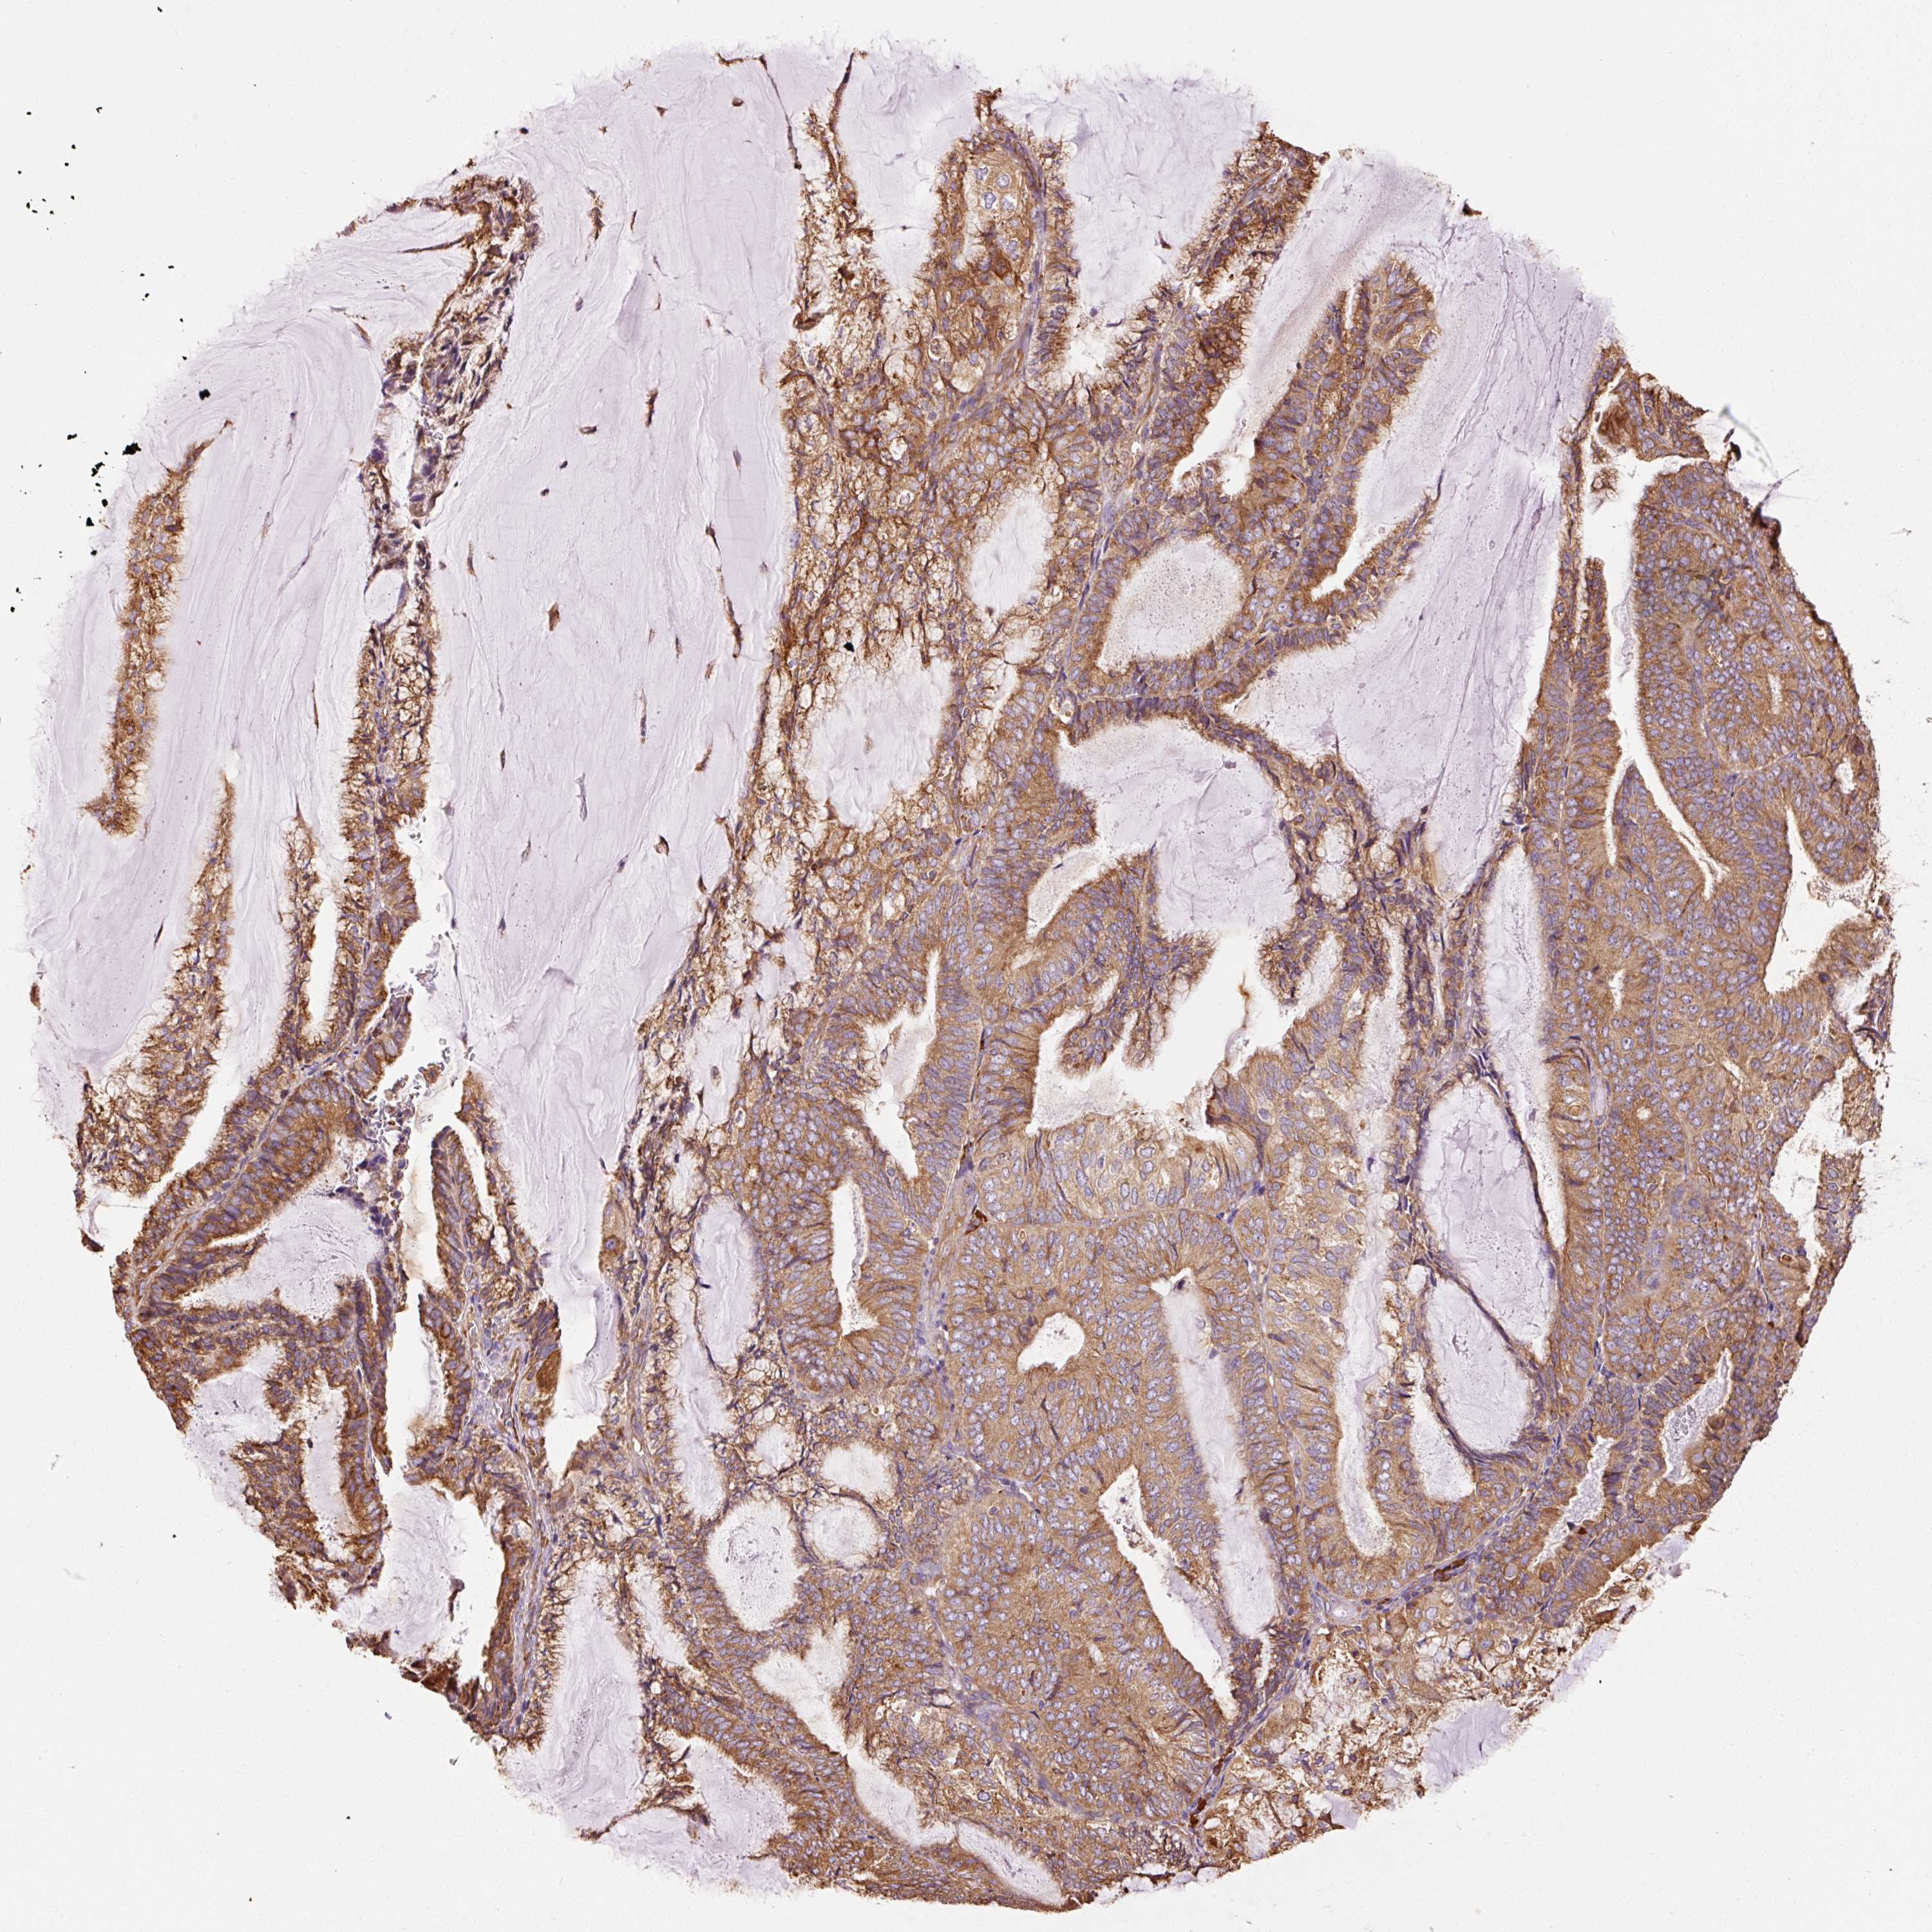

ENDOMETRIAL CANCER - Protein expressioni

A mouse-over function shows sample information and annotation data. Click on an image to view it in a full screen mode. Samples can be filtered based on level of antibody staining by selecting one or several of the following categories: high, medium, low and not detected. The assay and annotation is described here.

Note that samples used for immunohistochemistry by the Human Protein Atlas do not correspond to samples in the TCGA dataset.

Antibody stainingi

Antibody staining in the annotated cell types in the current human tissue is reported as not detected, low, medium, or high, based on conventional immunohistochemistry profiling in selected tissues. This score is based on the combination of the staining intensity and fraction of stained cells.

Each image is clickable and will lead to virtual microscopy that enables deeper exploration of all samples and also displays staining intensity scores, fraction scores and subcellular localization as well as patient and tissue information for each sample.

Antibody HPA044617

Antibody HPA052450

Staining

High

Medium

Low

Not detected

Intensity

Strong

Moderate

Weak

Negative

Quantity

>75%

75%-25%

<25%

None

Location

Nuclear

Cytoplasmic/membranous

Cytoplasmic/membranous,nuclear

Adenocarcinoma, NOS